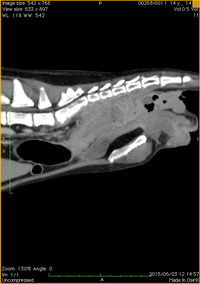

椎間板ヘルニア